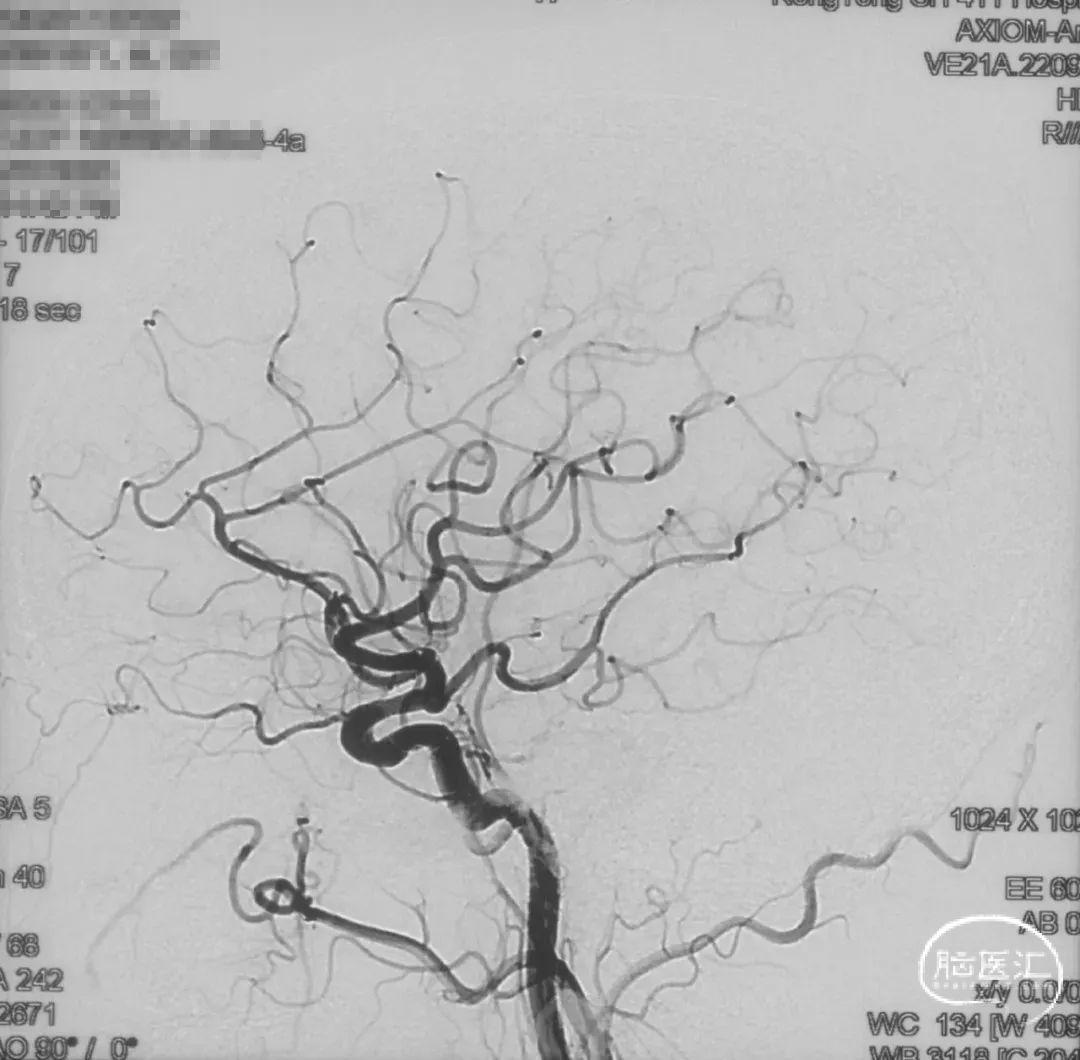

Echelon-10微导管在ASAHI 0.010微导丝导引下经右侧脑膜中动脉分支超选至瘘口,可见瘘口口径大,微导管直接越过瘘口,进入引流静脉起始部。

Marathon微导管在ASAHI 0.010微导丝导引下经右侧脑膜中动脉分支超选至瘘口近端。

经Marathon微导管手推造影明确微导管位于瘘口动脉端,Echelon-10微导管位于瘘口引流静脉起始端处扩张的静脉球内。

由于瘘口流量大,为了防止栓塞材料过度弥散,并逃逸至深静脉,首先通过Echelon-10微导管向静脉球内填入Feng 12/40、Feng 10/30两枚弹簧圈,限制后续液态栓塞材料仅在静脉起始部弥散。

随后回撤Echelon-10微导管,并通过Echelon-10微导管和Marathon微导管交替注入Onyx-34、Onyx-18,此时可见Onyx首先被血流冲至静脉球内,但被弹簧圈篮筐限制,并在瘘口范围内弥散。

通过“注射-停顿-再注射”,Onyx进一步在瘘口及供血动脉段和引流静脉起始部弥散满意

造影显示瘘口不显影,无静脉早显。

双侧颈外、颈内动脉正侧位造影瘘口均不显影

双侧椎动脉造影未见瘘口显影,可见广泛皮层静脉瘀滞

Onyx胶铸型显示瘘口形态。